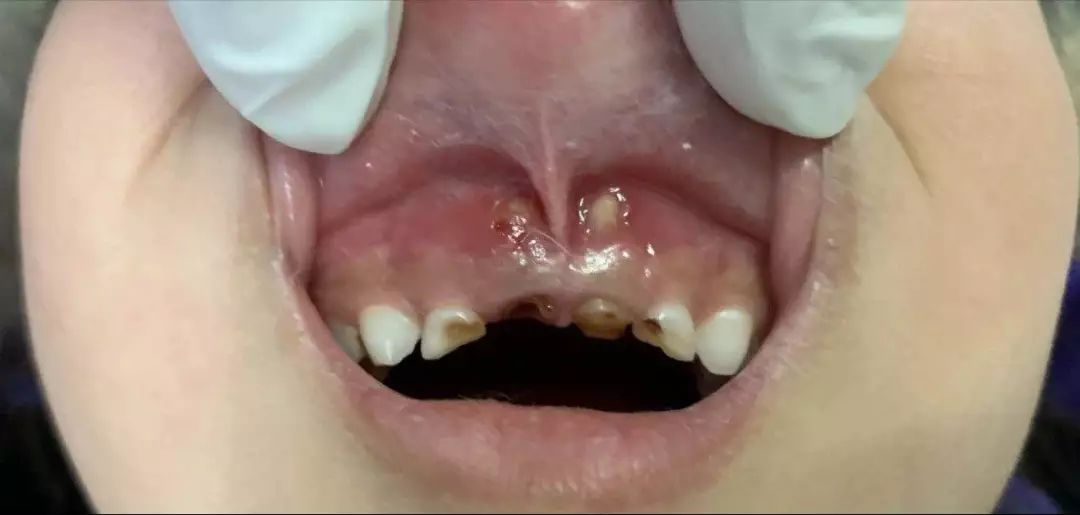

乳牙根尖周炎破壞牙槽骨并穿破粘膜

乳牙根穿破粘膜并形成創(chuàng)傷性潰瘍

而且有這樣的一種現(xiàn)實(shí),哪怕全口牙齲壞也鮮有家長為此主動去看牙醫(yī),更多的是當(dāng)孩子出現(xiàn)了劇烈牙痛或者牙齦上長出了令家長們驚恐的如圖示腫物(恐癌心理)才被迫就診,這是一種中國式特色——反正乳牙都是要換掉的,單純齲齒治不治無所謂。